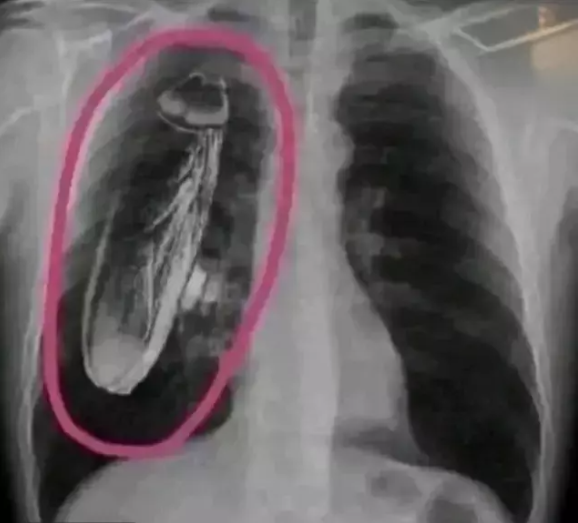

Rentgen müayinəsi zamanı sinəsində canlı tarakan olduğu deyilən şəxsin başına gələnlər eşidənləri həm təəccübləndirib, həm də güldürüb.

Belə ki, Keniya dövlət xəstəxanasında rentgen müayinəsindən keçən xəstəyə görüntülərdə sinə nahiyəsində canlı bir tarakan göründüyü bildirilib. İddialara görə, xəstəyə müalicə üçün Sinqapura getməsi tövsiyə edilib.

Daha sonra xəstə Sinqapura gedərək orada geniş müayinələrdən keçib. Nəticədə rentgendə göstərilən həşəratın xəstənin bədənində olmadığı üzə çıxıb.

Problemin Keniya xəstəxanasında istifadə edilən rentgen aparatının içərisində ilişib qalmış bir tarakandan qaynaqlandığı məlum olub.